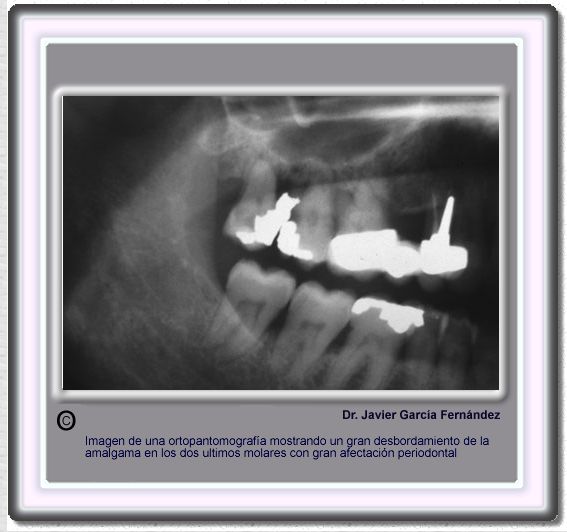

image337